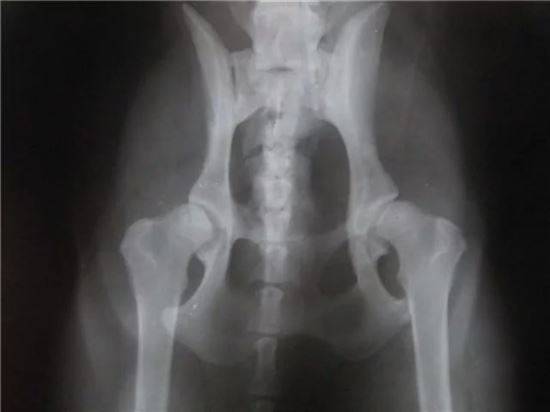

Заводчики собак во избежание дисплазии тазобедренных суставов выполняют длительную скрининговую проверку животных и только потом включают их в программу разведения. У кошек в возрасте до двух лет можно только предварительно оценить заболевание, окончательный диагноз ставится уже по достижении кошкой этого возраста. Исследование проводится с помощью рентгена и требует седации для того, чтобы достичь расслабления мышц и обеспечить правильную укладку.

Основными жалобами, возникающими у владельцев, чьи животные подверглись дисплазии суставов, являются: снижение подвижности кошки, выраженная слабость конечностей, подвергшихся заболеванию, шаткая походка, хромота, неправильная постановка конечностей. В ходе проведения диагностических тестов ветеринарный врач на приёме выявляет выраженную болезненность и ограничение диапазона движений при ортопедическом осмотре. Однако, стандартом диагностики дисплазии суставов у животных является рентген-исследование с применением анестезии. Дело в том, что именно при достижении седации животного возможно придать правильное положение конечностям и суставам, чтобы дать объективную оценку наличию или отсутствию дисплазии исследуемой области костно-суставного аппарата кошки.

Рентгенограммы должны выполняться под седалгией или под наркозом, чтобы обеспечить нужное положение сустава. Стандартный рентгенографический снимок делается, когда собака находится в дорсальном положении с вытянутыми параллельно задними конечностями, колени повернуты так, чтобы коленная чашечка находилась в центре блоковой борозды и симметрично расположенным тазом. Вентродорсальный вид должен включать два поясничных позвонка и оба колена. Тяжесть клинических симптомов не соотвествует тяжести рентгенографических изменений. Рентгенографическая съемка под нагрузкой поможет количественно оценить степень слабости сустава.

Стандартный вид: кошка лежит на спине, а ее задние лапы вытянуты прямо. Этот вид похож на оценочную рентгенограмму, необходимую для подтверждения OFA степени дисплазии бедра. (OFA классифицирует бедра по семи различным категориям: отличное, хорошее, удовлетворительное, пограничное, легкое, умеренное или тяжелое.) Для сертификации PennHIP выполняются дополнительные обзоры, которые учитывают измерения дряблости суставов, а также конформации тазобедренных суставов.

Рентгенограммы таза взрослой собаки с нормальными тазобедренными суставами, сравните их с приведенной ниже собакой с дисплазией тазобедренного сустава